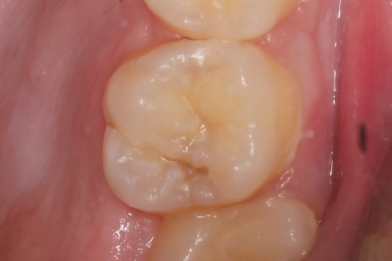

Д.12 лет. Жалобы на реакцию, на сладкое и холодное между зубами 16,15.

Колиш Максим Петрович

При осмотре обнаружен контактный кариес на зубах 16,15.

Лечение в один визит, восстановление функциональности композитной реставрацией. -